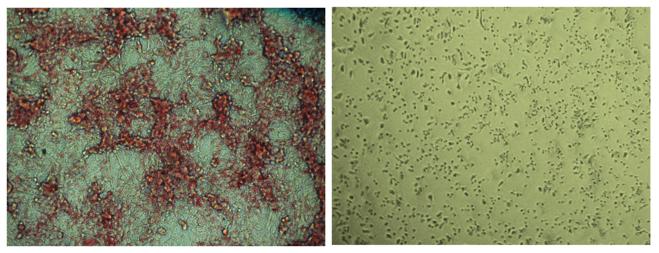

In multiple and extensive large-scale tests in both animal models of cancer and in transplanted human lung cancer cells, the results of the novel ACC inhibitor, dubbed ND-646, were far more promising than expected: tumor mass shrank by roughly two-thirds compared to untreated animals. And when the researchers paired ND-646 with one of the common treatments for non-small lung cancer called carboplatin, the anti-tumor response was even greater: a dramatic 87 percent of tumors were suppressed, compared to 50 percent with the standard treatment of carboplatin alone.